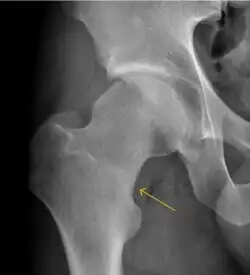

MRI has been shown to have 100% sensitivity and specificity in prospective studies of occult hip fractures. These fractures were diagnosed by bone marrow edema and a low signal fracture line, mainly on T1 or T2 weighted images (Figure 10).[1]

Figure 10:

Stress femoral neck fracture in a young athlete barely visible in X-ray film as a sclerotic line (arrow)[1] -

In this case, Tc 99 scintigraphy shows a band of uptake[1] -

Furthermore, T1 (left) and DP fat saturated (right) weighted MR images showed the fracture line and a pattern of edema.[1]